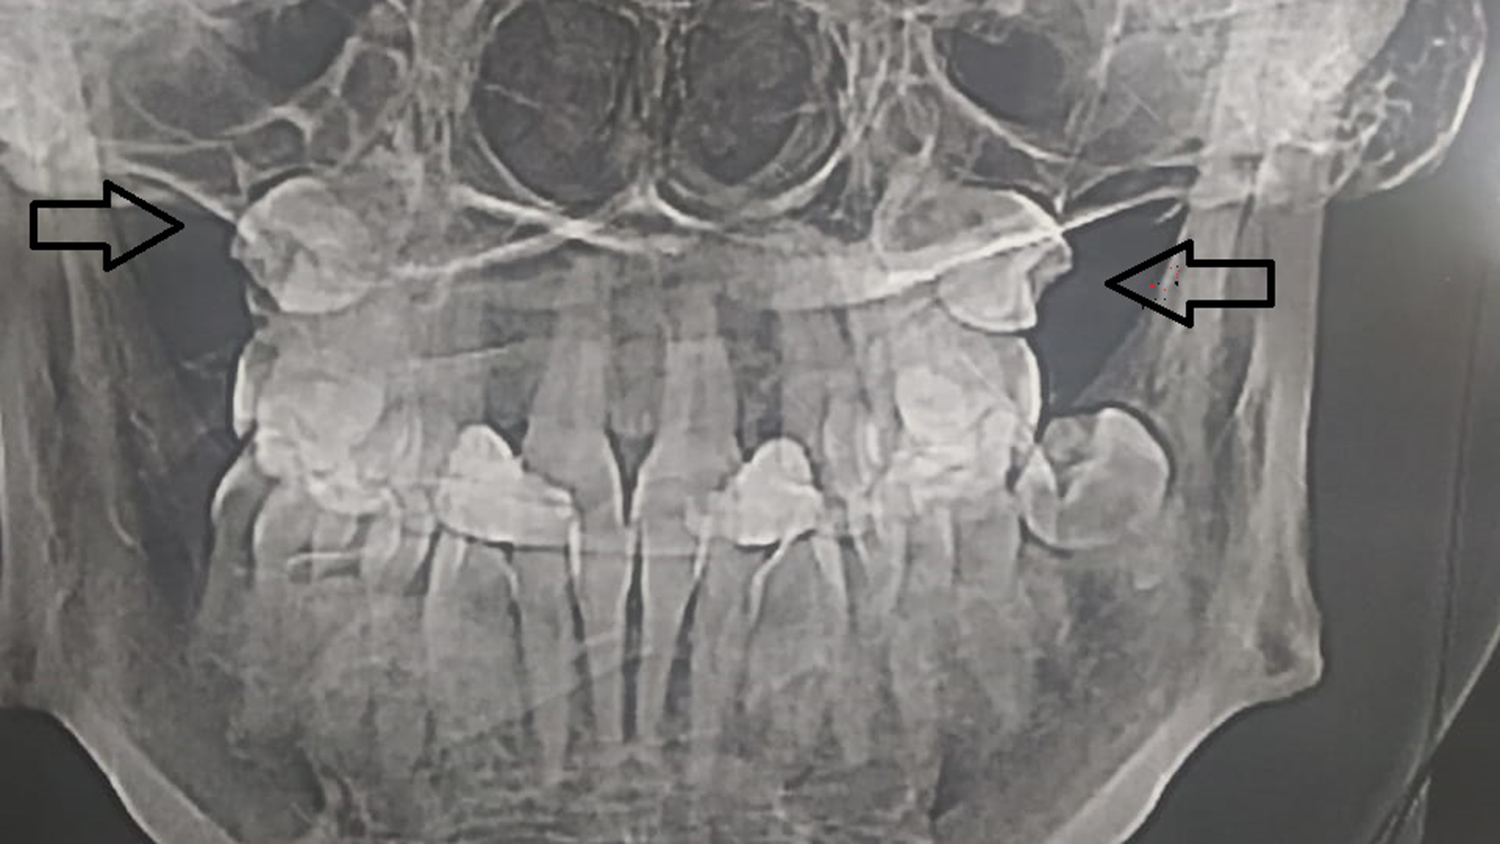

Жительница Самары обнаружила, что в гайморовых пазухах у нее выросли зубы, сообщает ГТРК «Самара».

Об этом женщина узнала, сделав МРТ. Выяснилось, что «четверки» (зубы которые идут после клыков) выросли вместо челюсти в носу.